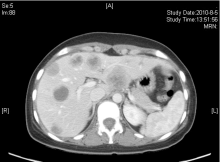

2009年5月患者自行发现右乳肿物, 遂于我院门诊行乳腺B超检查, 疑右乳腺癌保乳术后复发而收入院。入院后行PET检查示右乳腺癌保乳术后局部复发, 并全身多发性转移(见图1)。予化疗6周期后, 部分缓解。遂于2009年10月行右乳单纯切除术。术后病理结果示:(右侧) 乳腺浸润性导管癌, Ⅱ 级。肿瘤最大径无法准确评估; 未见明确脉管癌栓及神经束膜侵犯; 乳头及皮肤未见Paget’ s病; 各切缘及皮肤切缘均未见肿瘤。术后再予化疗2周期, 并予内分泌治疗, 嘱患者定期复查。